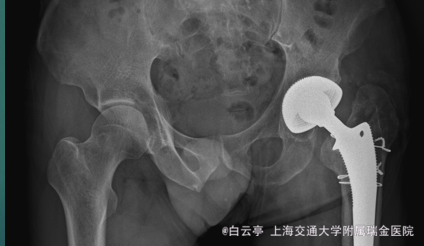

左侧髋关节置换术后疼痛2年余 患者因左侧髋关节疼痛2001年于我院全麻下行左侧髋关节置换术,手术顺利,出院后患者觉左髋关节疼痛肿胀,活动时明显,局部皮温升高,无寒战。患者近两年来左髋关节疼痛、活动受限加重,见既往手术切口,愈合良好,无裂口,无脓性分泌物流出,患者为求进一步治疗,门诊拟“左髋关节置换术后疼痛”收治入院。 患者自发病以来,神清精神可,胃纳睡眠可,二便无殊,体重无明显变化。

查体:神清,精神可,左侧髋部未见红肿,皮温高,屈曲稍受限,双下肢血运感觉可。 辅查:左侧x片提示

诊断:髋关节假体松动 治疗:左侧髋关节翻修术